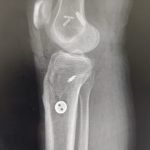

- Robotic Joint Replacement

- Knee Replacement Surgery

- Fracture Treatment